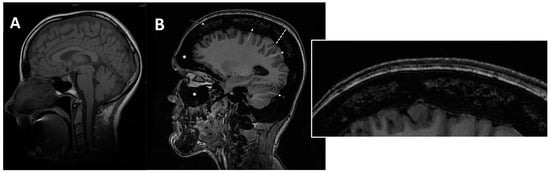

Another common group of complications is neurological involvement, which can be found in patients with ARO or IAO osteopetrosis. Imaging tools, MRIs above all, play a key role in the detection, evaluation, and follow up of neural structures damage. MRI is fundamental to assess cranial foramina (Figure 6) and brain abnormalities.

Figure 6. (A) axial MRI of a healthy young female (shown as comparison). (B) axial MRI (T2w*) of a 38-year-old female with a clinical-radiological diagnosis of osteopetrosis (ARO type); narrowing of both optic foramens can be noted (arrows) caused by a diffuse bone thickening. Diffuse bone thickening of cranial bones is associated with a marked ipointense signal intensity of all the skeletal structures related to the diffuse bone sclerosis (asterisks).

Figure 7. (A) axial MRI of a healthy young female (shown as comparison). (B) sagittal MRI (proton density sequence) in ARO-type osteopetrosis patient suffering from anaemia (Hb = 7g/dL) shows markedly reduced bone marrow space (arrows and enlargement on the right); diffuse calvarias bone thickening (dotted line), sclerosis (signal hypointensity), and obliteration of maxillary and frontal paranasal sinus (asterisks) can be noted.